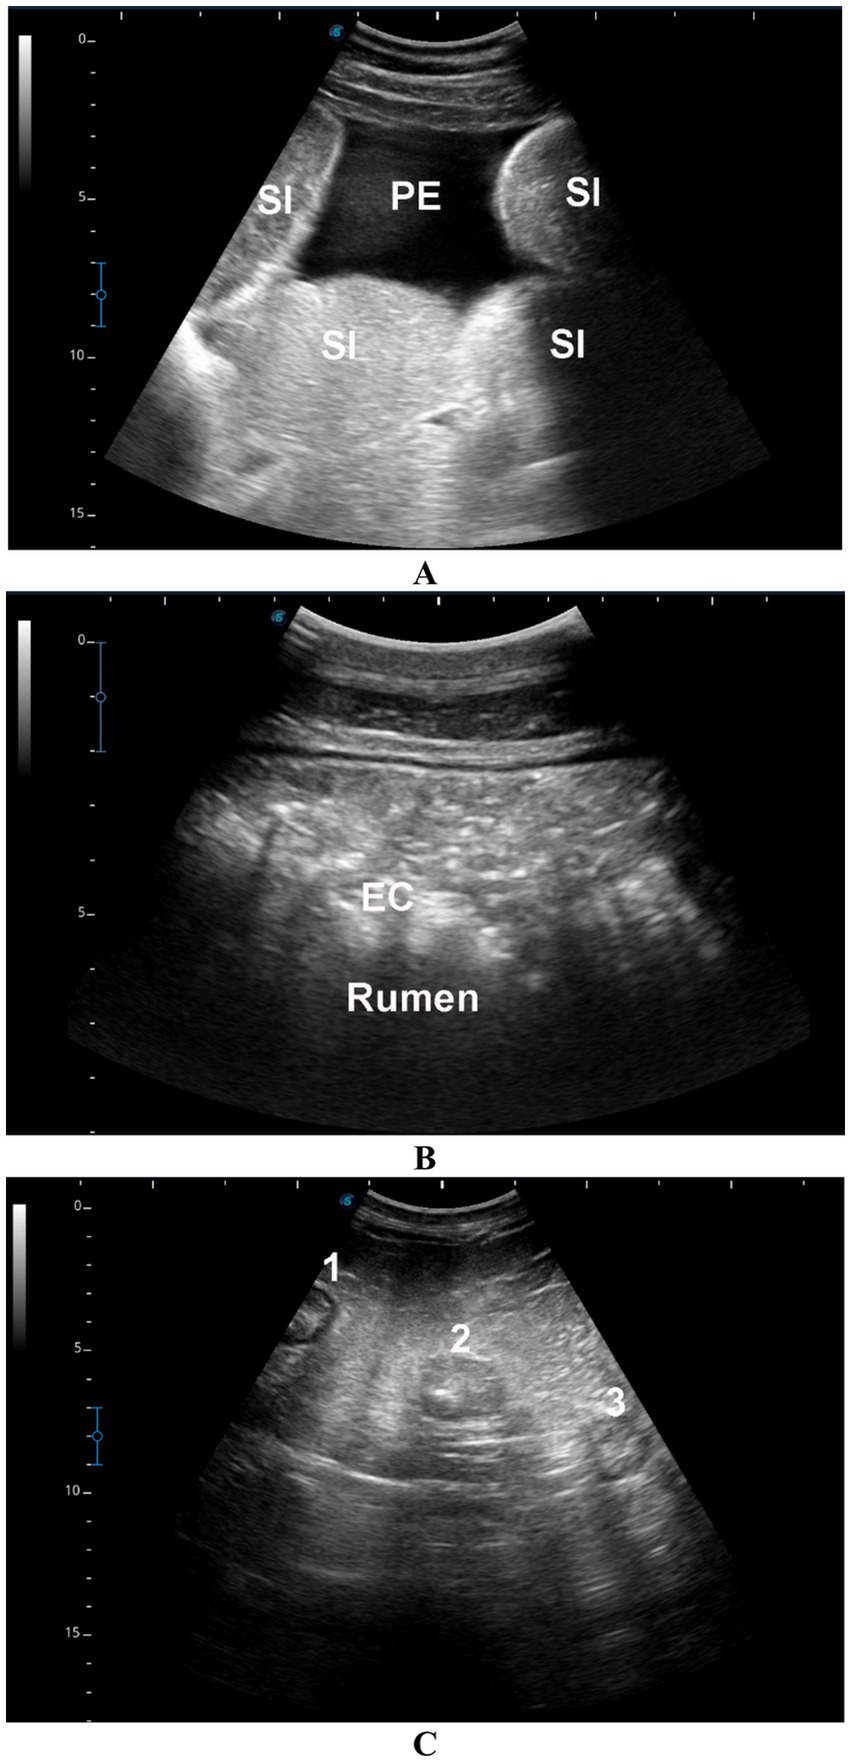

In camels with intestinal obstruction (group 1), ultrasonographic examination revealed markedly distended intestinal loops with either reduced or absent motility in 17 out of the 22 animals (77.3%). Peri-intestinal fluid accumulation was observed in 20 camels (90.9%) appearing hypoechoic, and in 2 camels (9.1%) appearing echogenic. In the impaction group (group 2), rumen contents were not visualized in 15 of the 20 camels (75%), while in the remaining 5 animals (25%), the contents appeared subjectively hyperechogenic. All camels with diarrhea (group 3) exhibited increased peristaltic activity. Among these, four camels (57.1%) showed sonographic thickening of the intestinal mucosa, while the remaining three camels (42.9%) had visibly enlarged mesenteric lymph nodes (Figure 4). None of the control camels (group 4) showed any abnormalities on GI or urinary tract ultrasonography.

Ultrasound images of the bovine abdomen. Image A shows prominent small intestines (SI) and peritoneal effusion (PE). Image B highlights edema of the ruminal wall (EC) and the rumen. Image C displays sections labeled one, two, and three, representing different cross-sectional views.

Figure 4. Ultrasonographic findings in camels with gastrointestinal disorders. (A) Distended small intestinal loops (SI) with mild echoic peritoneal effusion (PE) in a male camel with intestinal obstruction. (B) Echogenic rumen contents (EC) in a male camel with rumen impaction. (C) Enlarged mesenteric lymph nodes (labeled 1, 2, 3) in a female camel with a 7-day history of diarrhea.

Ultrasonography has proven to be an effective diagnostic modality in dromedary camel medicine, enabling evaluation of normal thoracic and abdominal organs as well as detection of various intra-abdominal pathologies (15, 7, 8, 2226, 28, 3033, 3645). In this study, ultrasound in camels with intestinal obstruction revealed markedly distended intestines with significantly reduced or absent motility, accompanied by hypoechoic to echogenic peri-intestinal fluid consistent with prior findings (28). In camels with gastric impaction, rumen contents were often difficult to visualize and appeared hyperechoic in approximately one-quarter of cases, findings in agreement with reports of rumen impaction secondary to pica or depraved appetite (32). Camels with diarrhea showed increased intestinal peristalsis, mucosal thickening, and enlarged mesenteric lymph nodes, similar to the changes reported in camels with paratuberculosis (33).